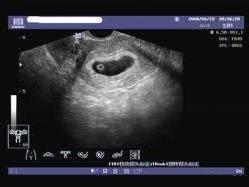

通過B超檢查發(fā)現(xiàn)胚胎未按照正常時間發(fā)育,如未按時出現(xiàn)胚芽、胎心等,可能是空孕囊的表現(xiàn)。